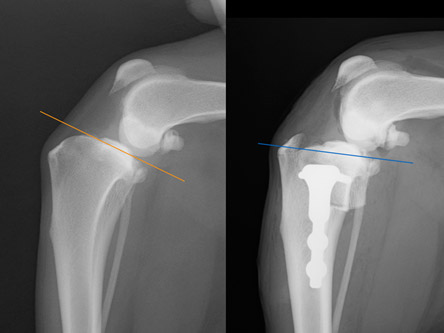

TPLO法は関節外法の時に必ず発生する骨関節炎の進行が低いといわれており、現在では前十字靭帯断裂に対する手術の第1選択法と言われています。TPLO法の原理は、脛骨の角度を調節することにより膝関節にかかる筋肉の力を変化させて前十字靭帯断裂により引き起こされる脛骨の前方変位を中和し、関節の動的な安定をもたらす手術方法です。

左:手術前

右:手術後 TPA(脛骨高平部の角度)の平坦化に注目

脛骨が前方に変位し、ファットパットサイン(関節炎)所見も認められます。

術後レントゲンです。体重のかかる脛骨高平角が水平に近づきました。これなら体重をかけても痛みはほとんどでないと判断されます。